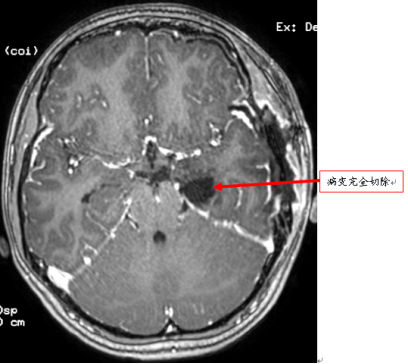

经充分评估和完善术前准备后,在术中电生理监测下,陈陆馗主任为小李行海绵状血管瘤切除术,彻底切除海绵状血管瘤及与异常脑电波形有关的病变。

术后MRI:病变完全切除。